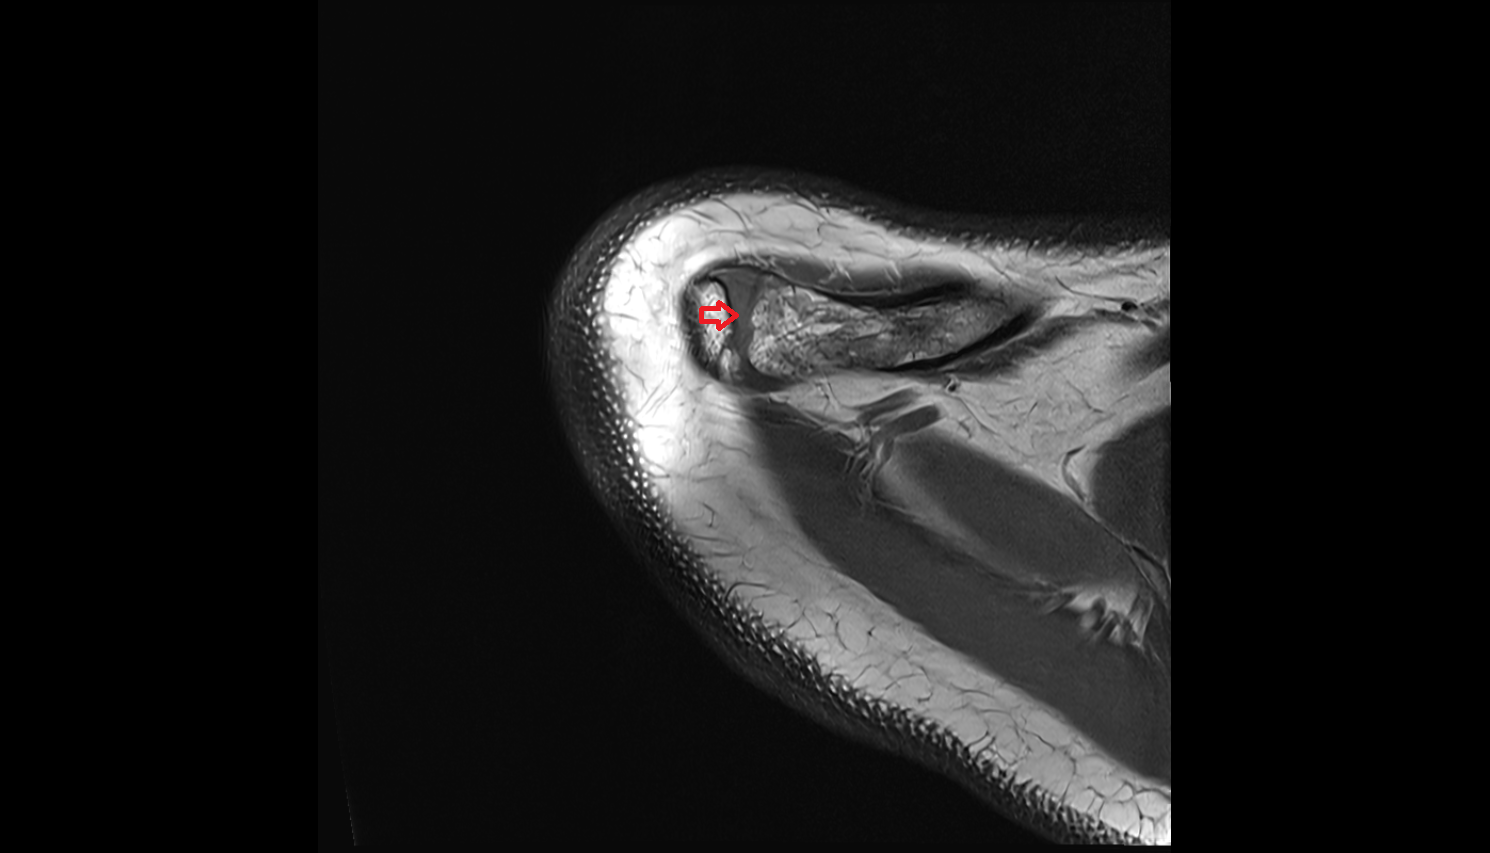

- Glenoid labrum

- Shoulder joint (glenohumeral joint)